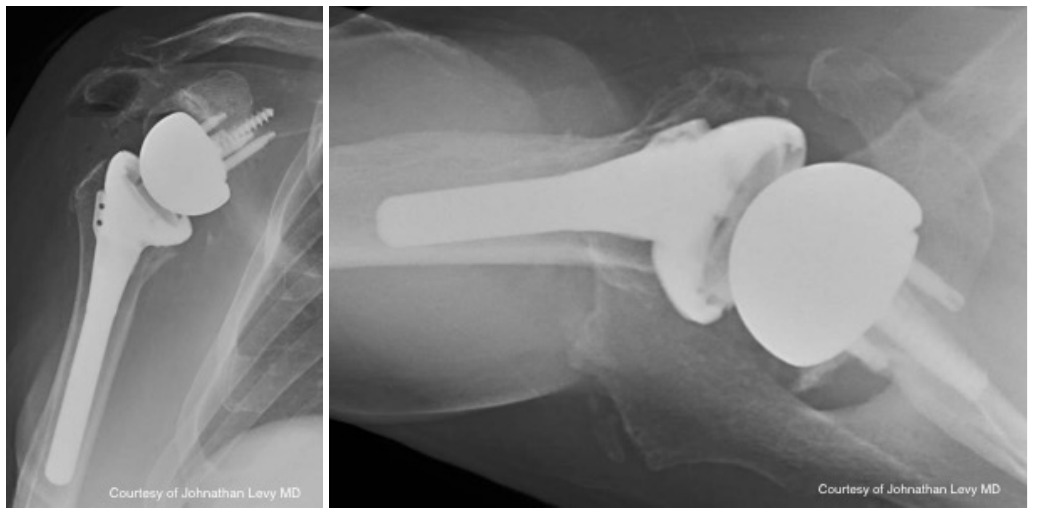

Case two is an 86-year-old female with long standing left shoulder pain and loss of function. Preoperative exam shows 70° of active forward flexion, neutral external rotation, and internal rotation to the lateral thigh. Radiographs (Figure 5) and CT scan (Figure 6) show significant posterior bone loss and retroversion with medialization of the joint line. Options include asymmetric reaming, an augmented component, or bone grafting. An augmented reverse baseplate was selected for this elderly female. Radiographs at six months show a well fixated baseplate with improvement of the pre-operative retroversion (Figure 7).